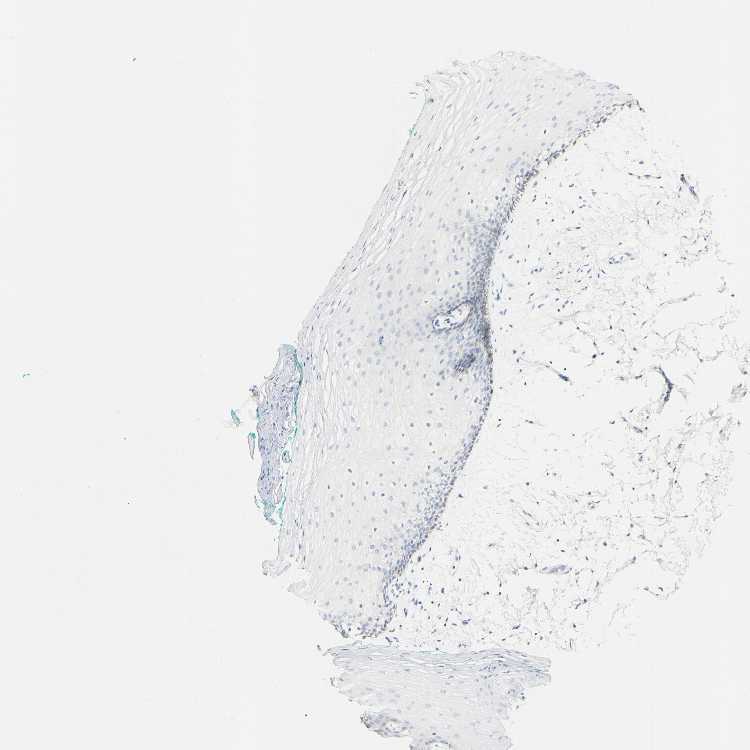

ORAL MUCOSA - Antibody stainingi

Antibody staining in the annotated cell types in the current human tissue is reported as not detected, low, medium, or high, based on conventional immunohistochemistry profiling in selected tissues. This score is based on the combination of the staining intensity and fraction of stained cells.

Each image is clickable and will lead to virtual microscopy that enables deeper exploration of all samples and also displays staining intensity scores, fraction scores and subcellular localization as well as patient and tissue information for each sample.

Antibody HPA011209

Squamous epithelial cells Not detected